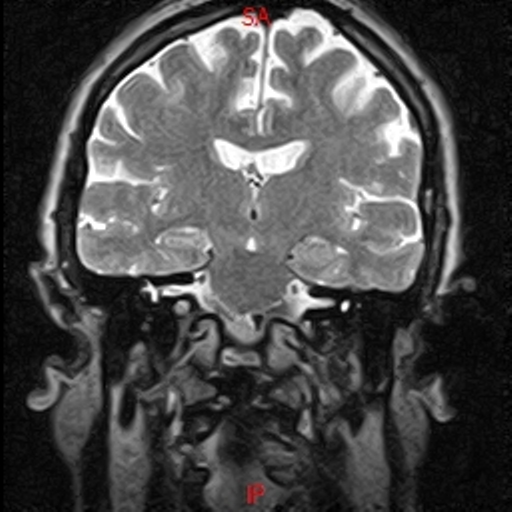

• RESONANCIA NORMAL CRANEAL FLAIR CORONAL